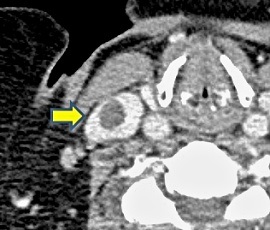

CT画像(矢印:血栓)